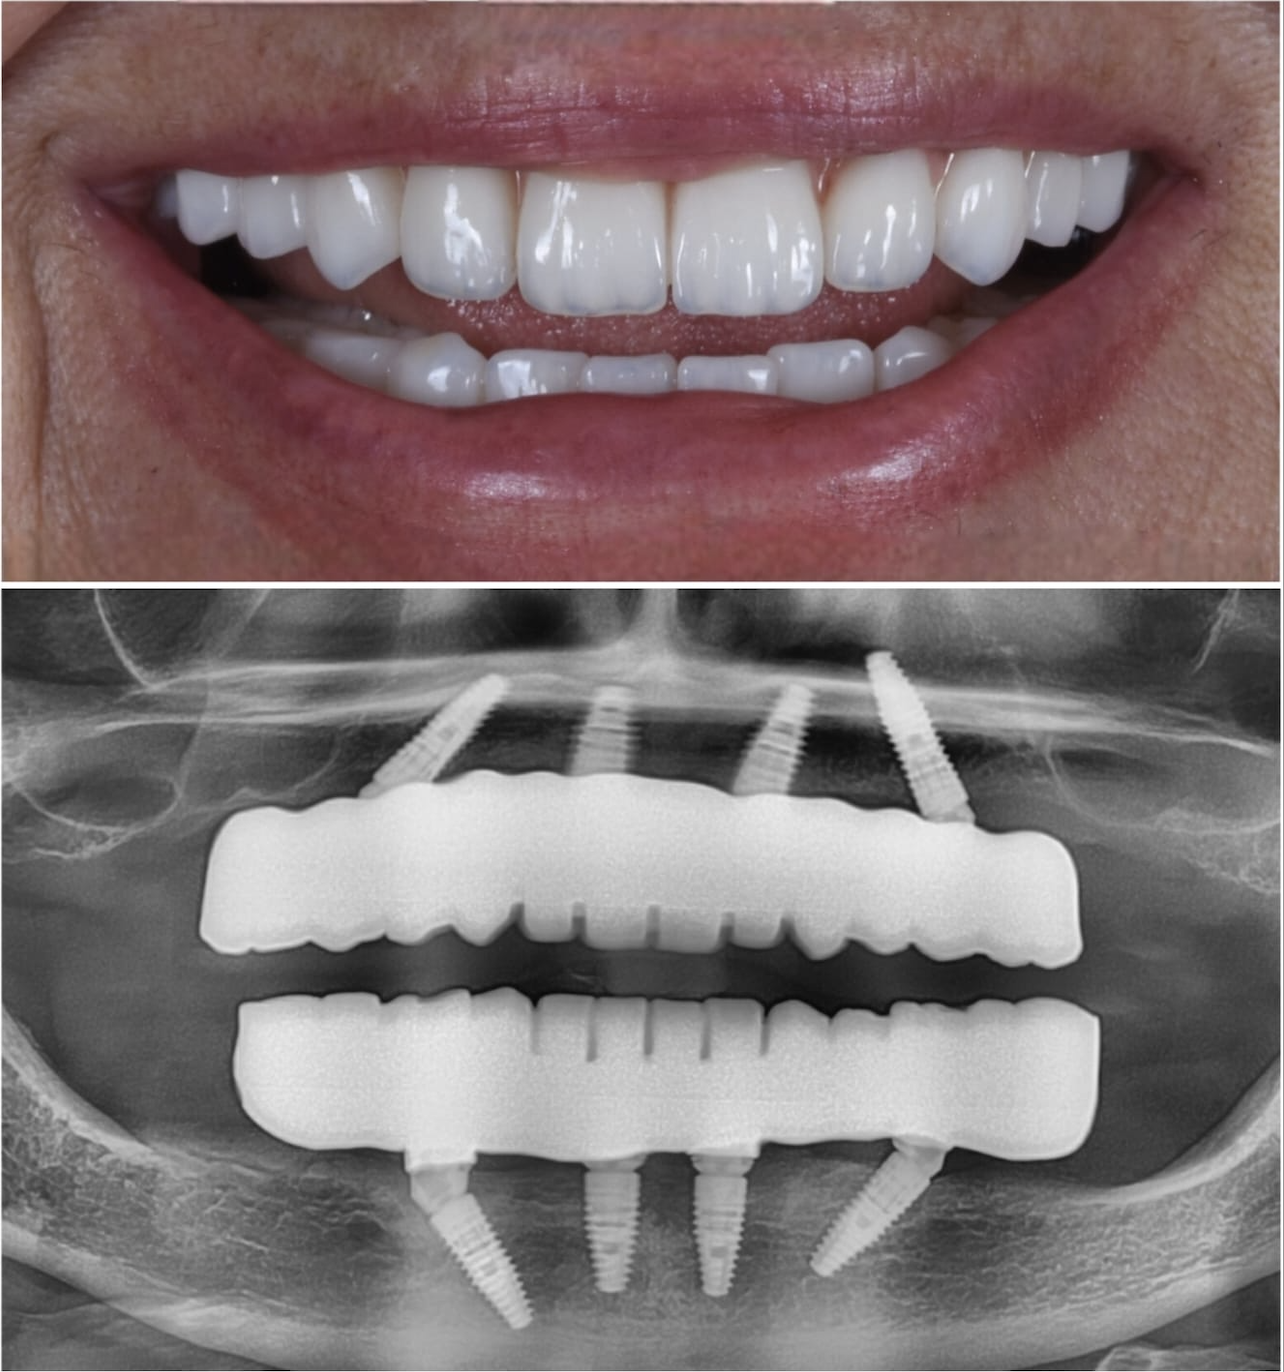

Immediate Loading Success

Before

Before treatment

After

After treatment